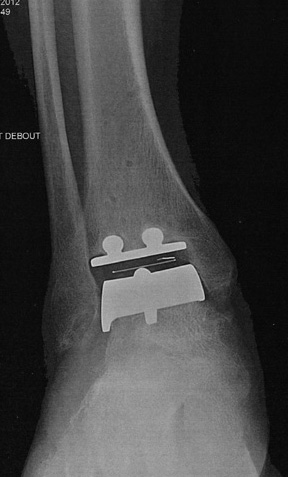

Ma prothèse

La dernière radio